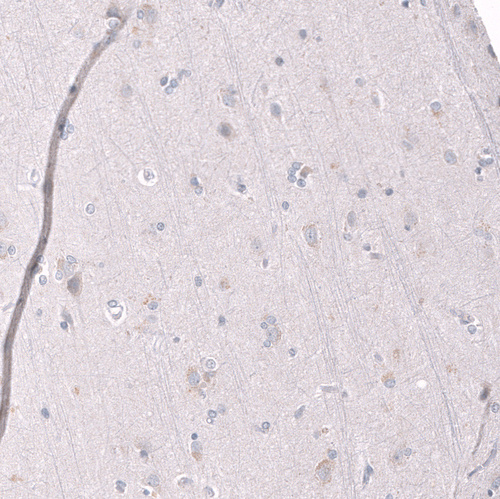

Immunohistochemistry analysis in human testis and cerebral cortex tissues using AMAb91752 antibody. Corresponding EZH2 RNA-seq data are presented for the same tissues.